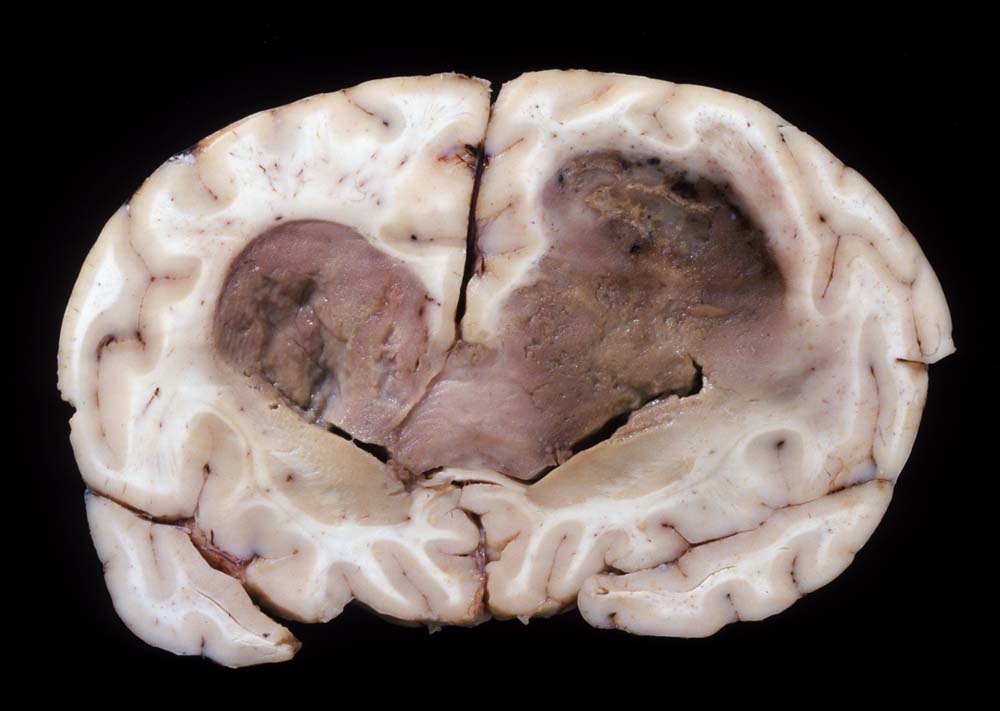

Morphologie:

Die Schnittfläche ist auffallend bunt. Dies ist bedingt durch ein Nebeneinander von graurotem vitalem Tumorgewebe, gelben Nekrosen, roten Einblutungen und gelegentlich grünlichen Gallertzysten.

Makroskopie